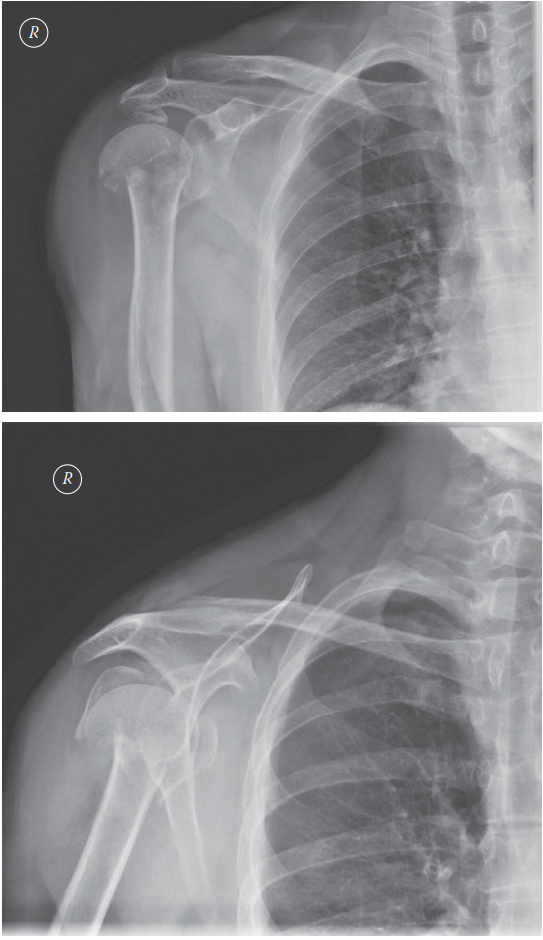

A 45-year-old man with epilepsy is brought to the emergency department following a sei- zure. He complains of…